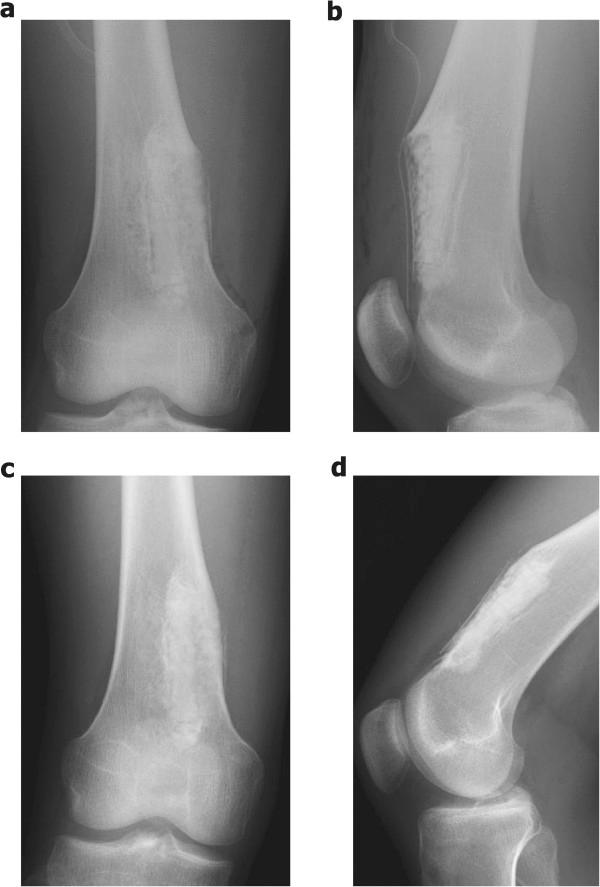

Periosteal chondromas are rare benign cartilaginous tumors that arise adjacent to the cortex beneath the periosteum. These lesions are usually slow-growing and rarely exceed 3 cm in the greatest dimension. Here, we describe a 17-year-old boy who had a giant periosteal chondroma of the right distal femur, which was treated with intralesional resection and intensive curettage. In addition, we report a novel application of a bioresorbable plate in the management of the large bone defect after resection of a benign bone tumor.